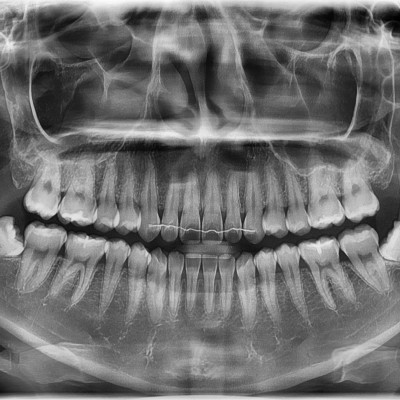

이턱퍼스트치과 사랑니 다양한 사랑니 당일발치가 가능합니다

작성자 이턱이 작성일 01-15 조회 29